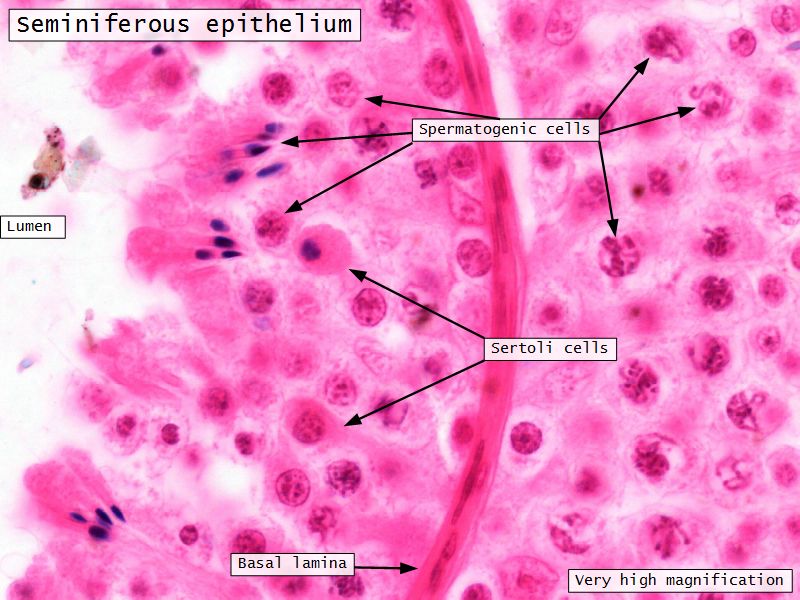

Seminiferous epithelium

- Two types of cells

- Spermatogenic cells

- Sertoli cells

Sertoli cells

- Complex columnar shape

- Basal lamina to lumen

- Irregular outline

- Envelope developing germ cells

- Large pale nucleus with indentations & large nucleolus

- Occludens junctions with adjacent cells

- Establish blood-testis barrier